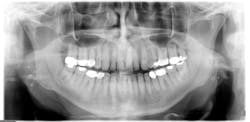

Radiographic assessment: Small, multiple, radiopaque, ill-defined, calcareous objects are seen on the radiograph (see Figure 1). The radiograph presented in this column was taken in 2015 of a 76-year-old male.

These opacities are not limited to the palatine tonsils but may also be seen in accessory lymphoid tissue. Sometimes what is referred to as "ghost images" appear on a pantomograph, making a pseudotonsillolith visible on the opposite side. This occurs because the object is located between the X-ray source and the center of rotation of the cassette. The patient may have oral calcifications bilaterally or unilaterally, so further evaluation is always needed.

Epidemiology: A study (Bamgbose et al., 2014) reported statistics on a group of patients presenting with tonsilloliths and other calcifications. Out of 124 selected cases of tonsillitis, 53 were males and 71 were females with a male-to-female ratio of 0.75:1.00. The age range was from 9.2 to 87 years old with a mean age of 52.6 years of age. The average size of the tonsillolith was 4 mm with a range of 3-11 mm. Other study data appear to indicate that these entities may occur in any age group with a purported average of 46.2 years of age.